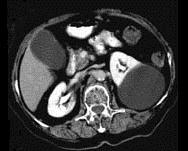

问题 女,38岁,左腰部胀痛不适,CT平扫+增强如图所示,下列说法正确的是 ( )

选项 A、考虑为左肾囊性肾癌 B、考虑为左肾囊肿 C、病灶边界清晰,表面光整 D、增强扫描皮质期和实质期该病灶均未见强化 E、平扫时可见左肾一类圆形囊性病灶

答案 BCDE